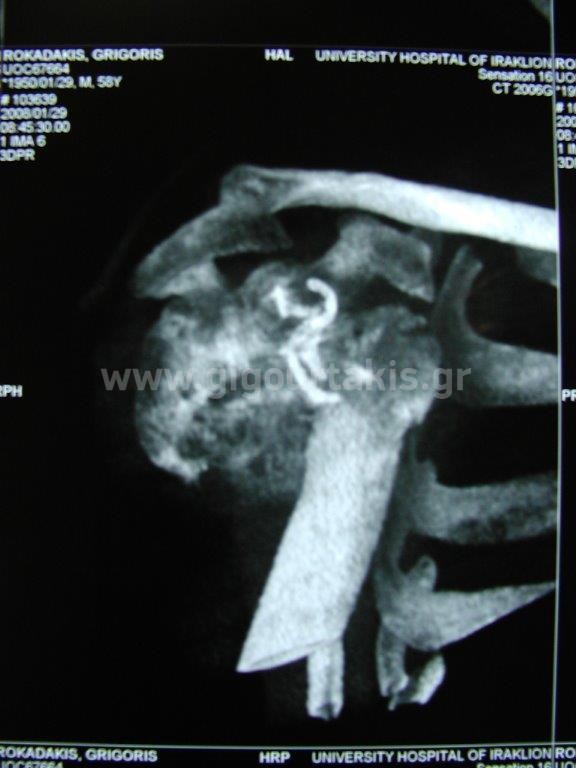

ΚΑΤΑΓΜΑ ΒΡΑΧΙΟΝΙΟΥ ΚΑΤΑΓΜΑ ΥΠΟΚΕΦΑΛΙΚΟ ΣΥΝΤΗΡΗΤΙΚΑ ΠΕΡΙΣΤΑΤΙΚΟ 1 01. 02. 03.ΑΡΧΙΚΗ ΑΠΑΓΩΓΗ ΩΜΟΥ 04.ΑΡΧΙΚΗ ΕΞΩ ΣΤΡΟΦΗ ΩΜΟΥ 06.ΑΡΧΙΚΗ ΕΣΩ ΣΤΡΟΦΗ ΩΜΟΥ 11.ΤΕΛΙΚΗ ΑΠΑΓΩΓΗ ΩΜΟΥ 12.ΤΕΛΙΚΗ ΟΠΙΣΘΙΑ ΠΡΟΣΑΓΩΓΗ ΩΜΟΥ 14.ΤΕΛΙΚΗ ΕΣΩ ΣΤΡΟΦΗ ΩΜΟΥ ΠΕΡΙΣΤΑΤΙΚΟ 2 01. 02. 04.ΑΡΧΙΚΗ ΑΠΑΓΩΓΗ ΒΡΑΧΙΟΝΙΟΥ 05.ΑΡΧΙΚΗ ΕΞΩ ΣΤΡΟΦΗ ΒΡΑΧΙΟΝΙΟΥ 06.ΑΡΧΙΚΗ ΟΠΙΣΘΙΑ ΠΡΟΣΑΓΩΓΗ ΒΡΑΧΙΟΝΙΟΥ 07.ΤΕΛΙΚΗ ΚΑΜΨΗ ΩΜΟΥ 2 08.ΤΕΛΙΚΗ ΑΠΑΓΩΓΗ ΩΜΟΥ 1 10.ΤΕΛΙΚΗ ΕΞΩ ΣΤΡΟΦΗ ΩΜΟΥ 2 11.ΤΕΛΙΚΗ ΟΠΙΣΘΙΑ ΠΡΟΣΑΓΩΓΗ ΩΜΟΥ 1 ΠΕΡΙΣΤΑΤΙΚΟ 3 01 Στις κατηγορίες:ΑΝΩ ΑΚΡΟ, ΣΥΝΤΗΡΗΤΙΚΑ, ΚΑΤΑΓΜΑ ΥΠΟΚΕΦΑΛΙΚΟ ΒΡΑΧΙΟΝΙΟΥ, ΚΑΤΑΓΜΑ ΒΡΑΧΙΟΝΙΟΥ, ΩΜΙΚΗ ΖΩΝΗ ΒΡΑΧΙΟΝΙΟ, ΚΑΤΑΓΜΑTA